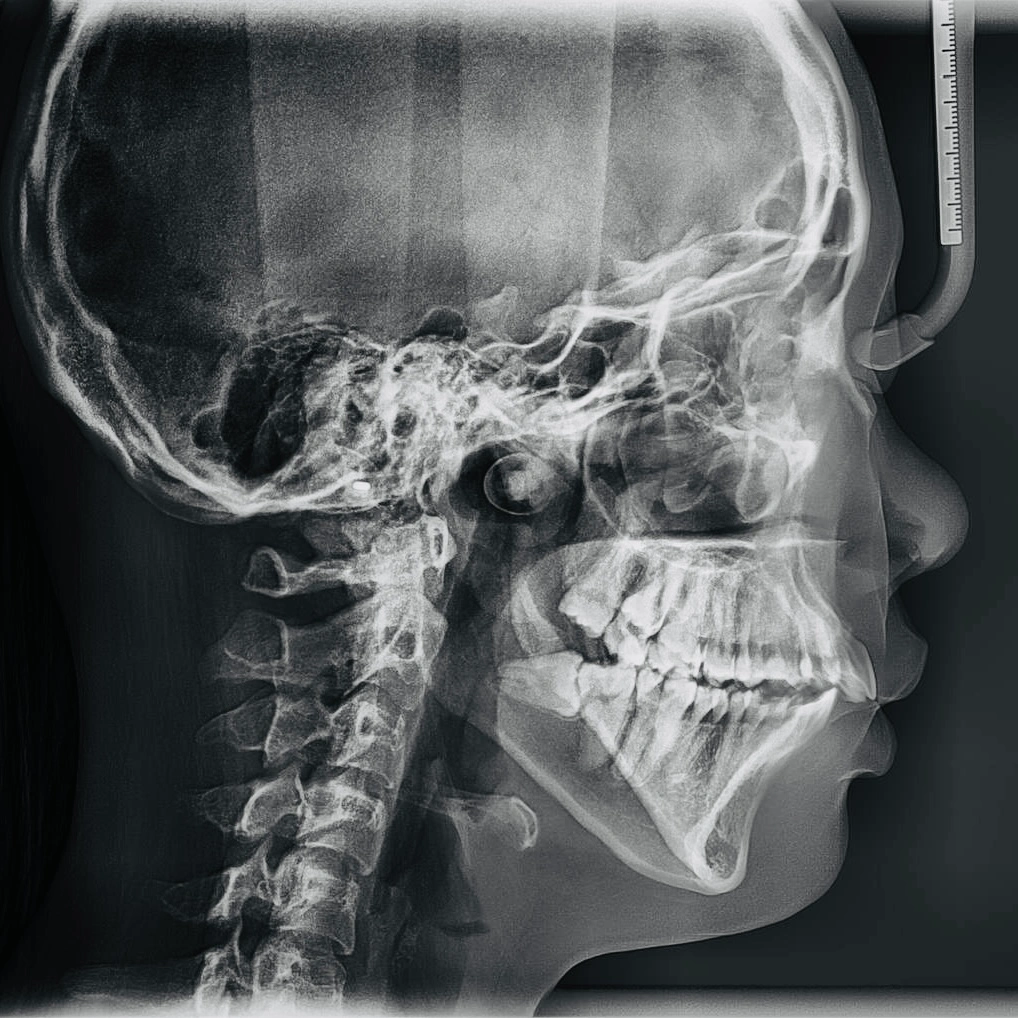

Lateral cephalometric dental X-ray showing side view of skull, teeth, and cervical spine

A lateral cephalometric X-ray used for orthodontic diagnosis and treatment planning

A Cephalometric X-ray (also called a “ceph”) is a lateral (side-view) X-ray of the entire head, capturing your teeth, jaw, nasal passages, and soft tissues in a single image. It shows not just the position of your teeth, but how they relate to your jaw and skull.

Unlike most dental X-rays that focus on the teeth and roots, the cephalometric X-ray provides a bigger anatomical picture, especially useful when we need to plan for more than just fillings or cleanings.

For patients considering orthodontics or jaw surgery, this image is absolutely essential. It helps our dentists and orthodontists visualize your profile and skeletal relationships to design a personalized, safe, and effective treatment plan.